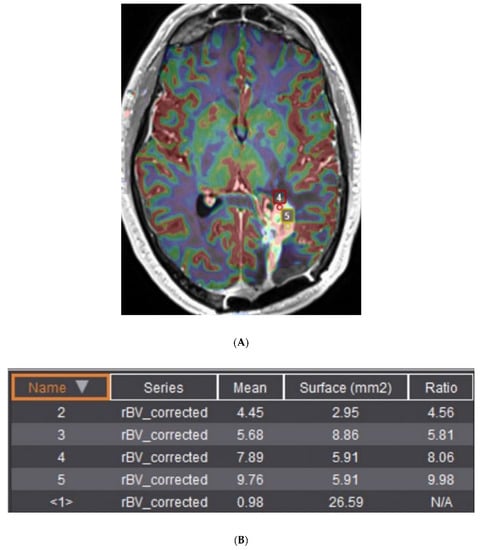

- Jones, K.K.; Maziero, D.; Ford, J.C.; Stoyanova, R.; Goryawala, M.; Diwanji, T.; Mellon, E.A. MRI-guided radiotherapy identifies early pseudoprogression of glioblastoma. Res. Sq. 2020. [Google Scholar] [CrossRef]